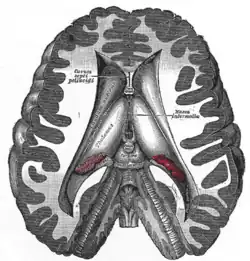

Transverse dissection showing the ventricles of the brain.

The four cavities of the human brain are called ventricles.[6] The two largest are the lateral ventricles in the cerebrum, the third ventricle is in the diencephalon of the forebrain between the right and left thalamus, and the fourth ventricle is located at the back of the pons and upper half of the medulla oblongata of the hindbrain. The ventricles are concerned with the production and circulation of cerebrospinal fluid.[7]

- lateral ventricles right and left (one for each hemisphere)

- third ventricle

- fourth ventricle